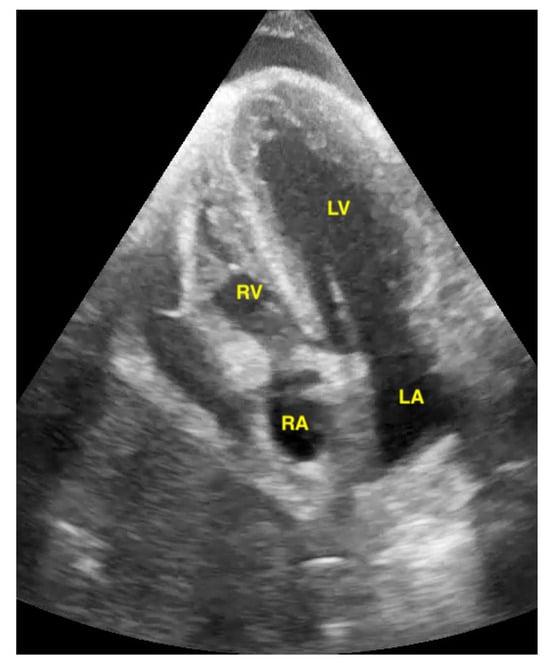

Figure 9.

Pericardial effusion in apical four chamber view compresses the right atrium slightly (RA = right atrium, LA = left atrium, RV = right ventricle, LV = left ventricle).

Figure 10.

Pericardial effusion in subxiphoidal view compresses the right ventricle.